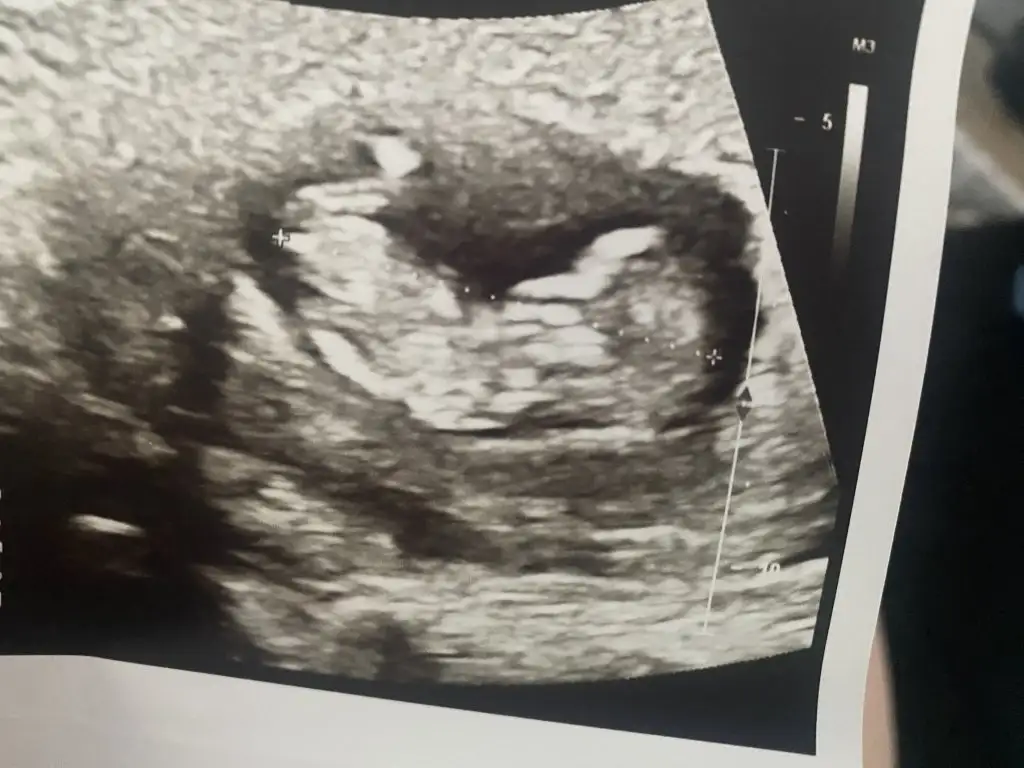

Kaçıncı haftadasın canımSelamlar herkese, bugün fetal dna için kan verdim çok heyecanlıyım sonuç için umarım hepimiz güzel haberler alırızUltrasonda bebişe bakarken bir çıkıntı gördük dr %90 erkek dedi şoktayım en başından beri kız hissediyordum Sağlıklı olsunlar tabiki ne olursa olsun çok seveceğiz ama ne çin takvimi ne tatlı atlı muhabbeti tutmadı bende

11+4 canımKaçıncı haftadasın canım

Bizdede çıkıntı görünmedi emin olmak için 1 ay sonra tekrar bakılcak gönlümüzdeki kız nasipseSelamlar herkese, bugün fetal dna için kan verdim çok heyecanlıyım sonuç için umarım hepimiz güzel haberler alırızUltrasonda bebişe bakarken bir çıkıntı gördük dr %90 erkek dedi şoktayım en başından beri kız hissediyordum Sağlıklı olsunlar tabiki ne olursa olsun çok seveceğiz ama ne çin takvimi ne tatlı atlı muhabbeti tutmadı bende

Gönlünüze göre olsun inşallahBizdede çıkıntı görünmedi emin olmak için 1 ay sonra tekrar bakılcak gönlümüzdeki kız nasipse

Bugun sata göre 7+5 im

Dün kalp atışını duyduk

Geç döllenme dedi 6 haftalık gbi duruyor dedi

Bunun dışında sağ yumurtalığımda 7cm kanamalı kistım var, içi kan dolu

Doktor takip edecegız dedi, küçülebılırmış yada öylece kalablırmış

Ona braz moralım bozuk